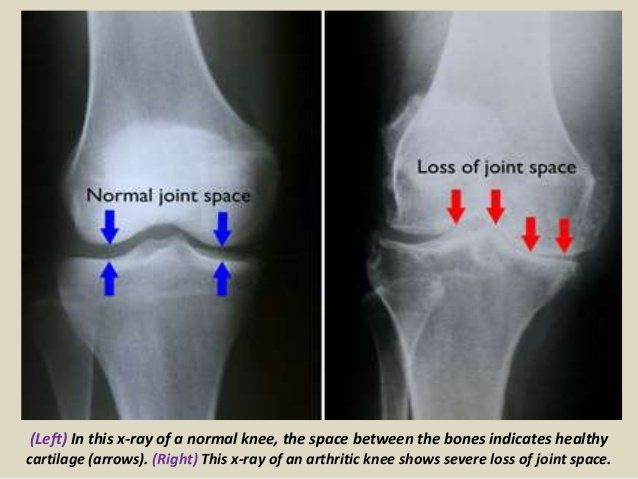

Osteoarthritis is commonly referred to as the “wear and tear” degenerative joint disease. It typically results from the gradual loss of cartilage - the tough connective tissue that is within/between joints. In a way too simple analogy of this complex mechanism - this cartilage serves as essentially a shock absorber preventing direct shear force or “bone on bone” pressure. Once the shock absorber is weakened/gone – trauma will slowly lead to inflammation and erosion of the joint (PAIN!). This leads to a pretty straightforward question - is there a way to repair or at the least slow down the decline of cartilage? Enter Glucosamine - which is an amino sugar and precursor in the synthesis of glycosylated lipids and proteins. It is a natural compound that exists in our cartilage.

Osteoarthritis is one of the most common medical conditions in the world and is commonly referred to as “wear and tear” degenerative joint disease. It typically results from the gradual loss of cartilage within/between joints. This cartilage serves as a type of shock absorber preventing direct shear force and “bone on bone” pressure. Once the shock-absorber is gone it will slowly lead to inflammation and erosion of the joint. US Centers for Disease Control data estimate approx 60 million people with doctor diagnosed arthritis – and remember many people live with joint aches/pain without seeing a physician or getting a formal diagnosis of OA. Sadly the symptoms of OA simply do not stop at the joint. The Arthritis Foundation notes that individuals with OA are almost three times more likely to develop cardiovascular disease (CVD) or heart failure than those without OA. Also, people with osteoarthritis experience as much as 30 percent more falls and have a 20 percent greater risk of fracture than those without OA. These links are especially strong when arthritis is in certain weight bearing/balance joints, such as the knee/back/hip. It makes sense – pain/weakness especially in our stabilizing joints such as knees/hips/spine will limit mobility and lead to risk factors such as weight gain, cardiovascular disease, diabetes coupled with stability issues. These patients would have difficulty following American Heart Association recommendation s that recommend increased physical activity and note that becoming more active can help lower blood pressure and also boost levels of good cholesterol. Without regular physical activity, the body slowly loses its strength, stamina and ability to function well - People who are physically active live about 7 years longer than those who are not active and are obese (American Heart Association). Studies have shown that adults who are inactive/minimally active more than 4 hours a day had a 46% increased risk of death from any cause and an 80% increased risk of death from cardiovascular disease! So now let us focus on some of the clinical presentations of Osteoarthritis (OA). In general there is a marked variability of disease expression. Although most patients present with joint pain and functional limitations, the age of disease onset, sequence of joint involvement, and disease progression vary from person to person. OA ranges from an asymptomatic, incidental finding on clinical or radiologic examination to a progressive disabling disorder eventually culminating in "joint failure" with impaired mobility and quality of life. The primary symptoms of osteoarthritis (OA) are joint pain, stiffness, and motor restriction. Symptoms usually present in just one or a few joints in a middle-aged or older person. Other manifestations in patients with OA include sequelae such as muscle weakness, poor balance, and associated conditions such as fibromyalgia (a disorder characterized by widespread musculoskeletal pain accompanied by fatigue, sleep, memory and mood issues).